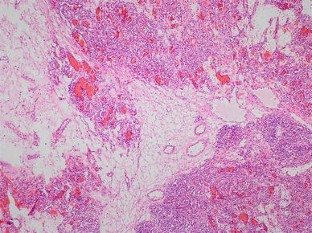

We report a case of a lobular capillary hemangioma in a 66-year-old man, who presented with left testicular pain, with an asymptomatic incidental right testicular lesion found on ultrasonography. The sonographic examination demonstrated a heterogeneous mainly iso-echoic intratesticular lesion with marked vascularity on the color Doppler examination. Further evaluation with contrast-enhanced ultrasound and strain elastography was performed; the multiparametric imaging suggested a benign tumor. The multidisciplinary team decision with patient consent was to perform a radical orchiectomy with subsequent histopathology confirming a benign lobular capillary hemangioma.

Fig. 4